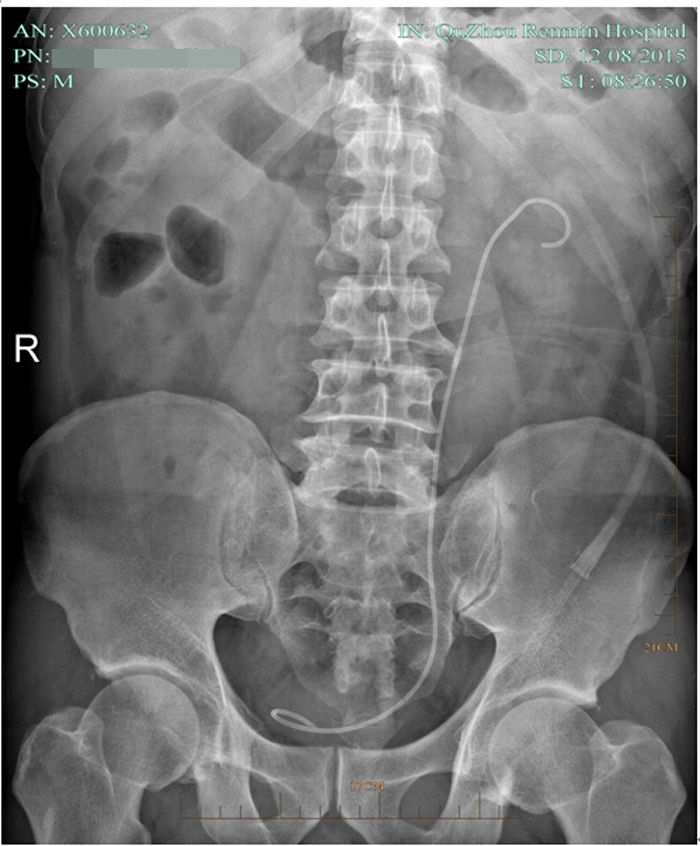

術(shù)后復(fù)查平片

術(shù)后復(fù)查泌尿系平片

??? 術(shù)后第七天,復(fù)查泌尿系平片無(wú)結(jié)石殘留,拔了腎造瘺管出院。因?yàn)槟I結(jié)石手術(shù)都需要放置輸尿管支架管,出院時(shí)護(hù)士叮囑出院后要多喝水,避免活動(dòng)過(guò)多引起血尿,1個(gè)月后來(lái)拔支架管。